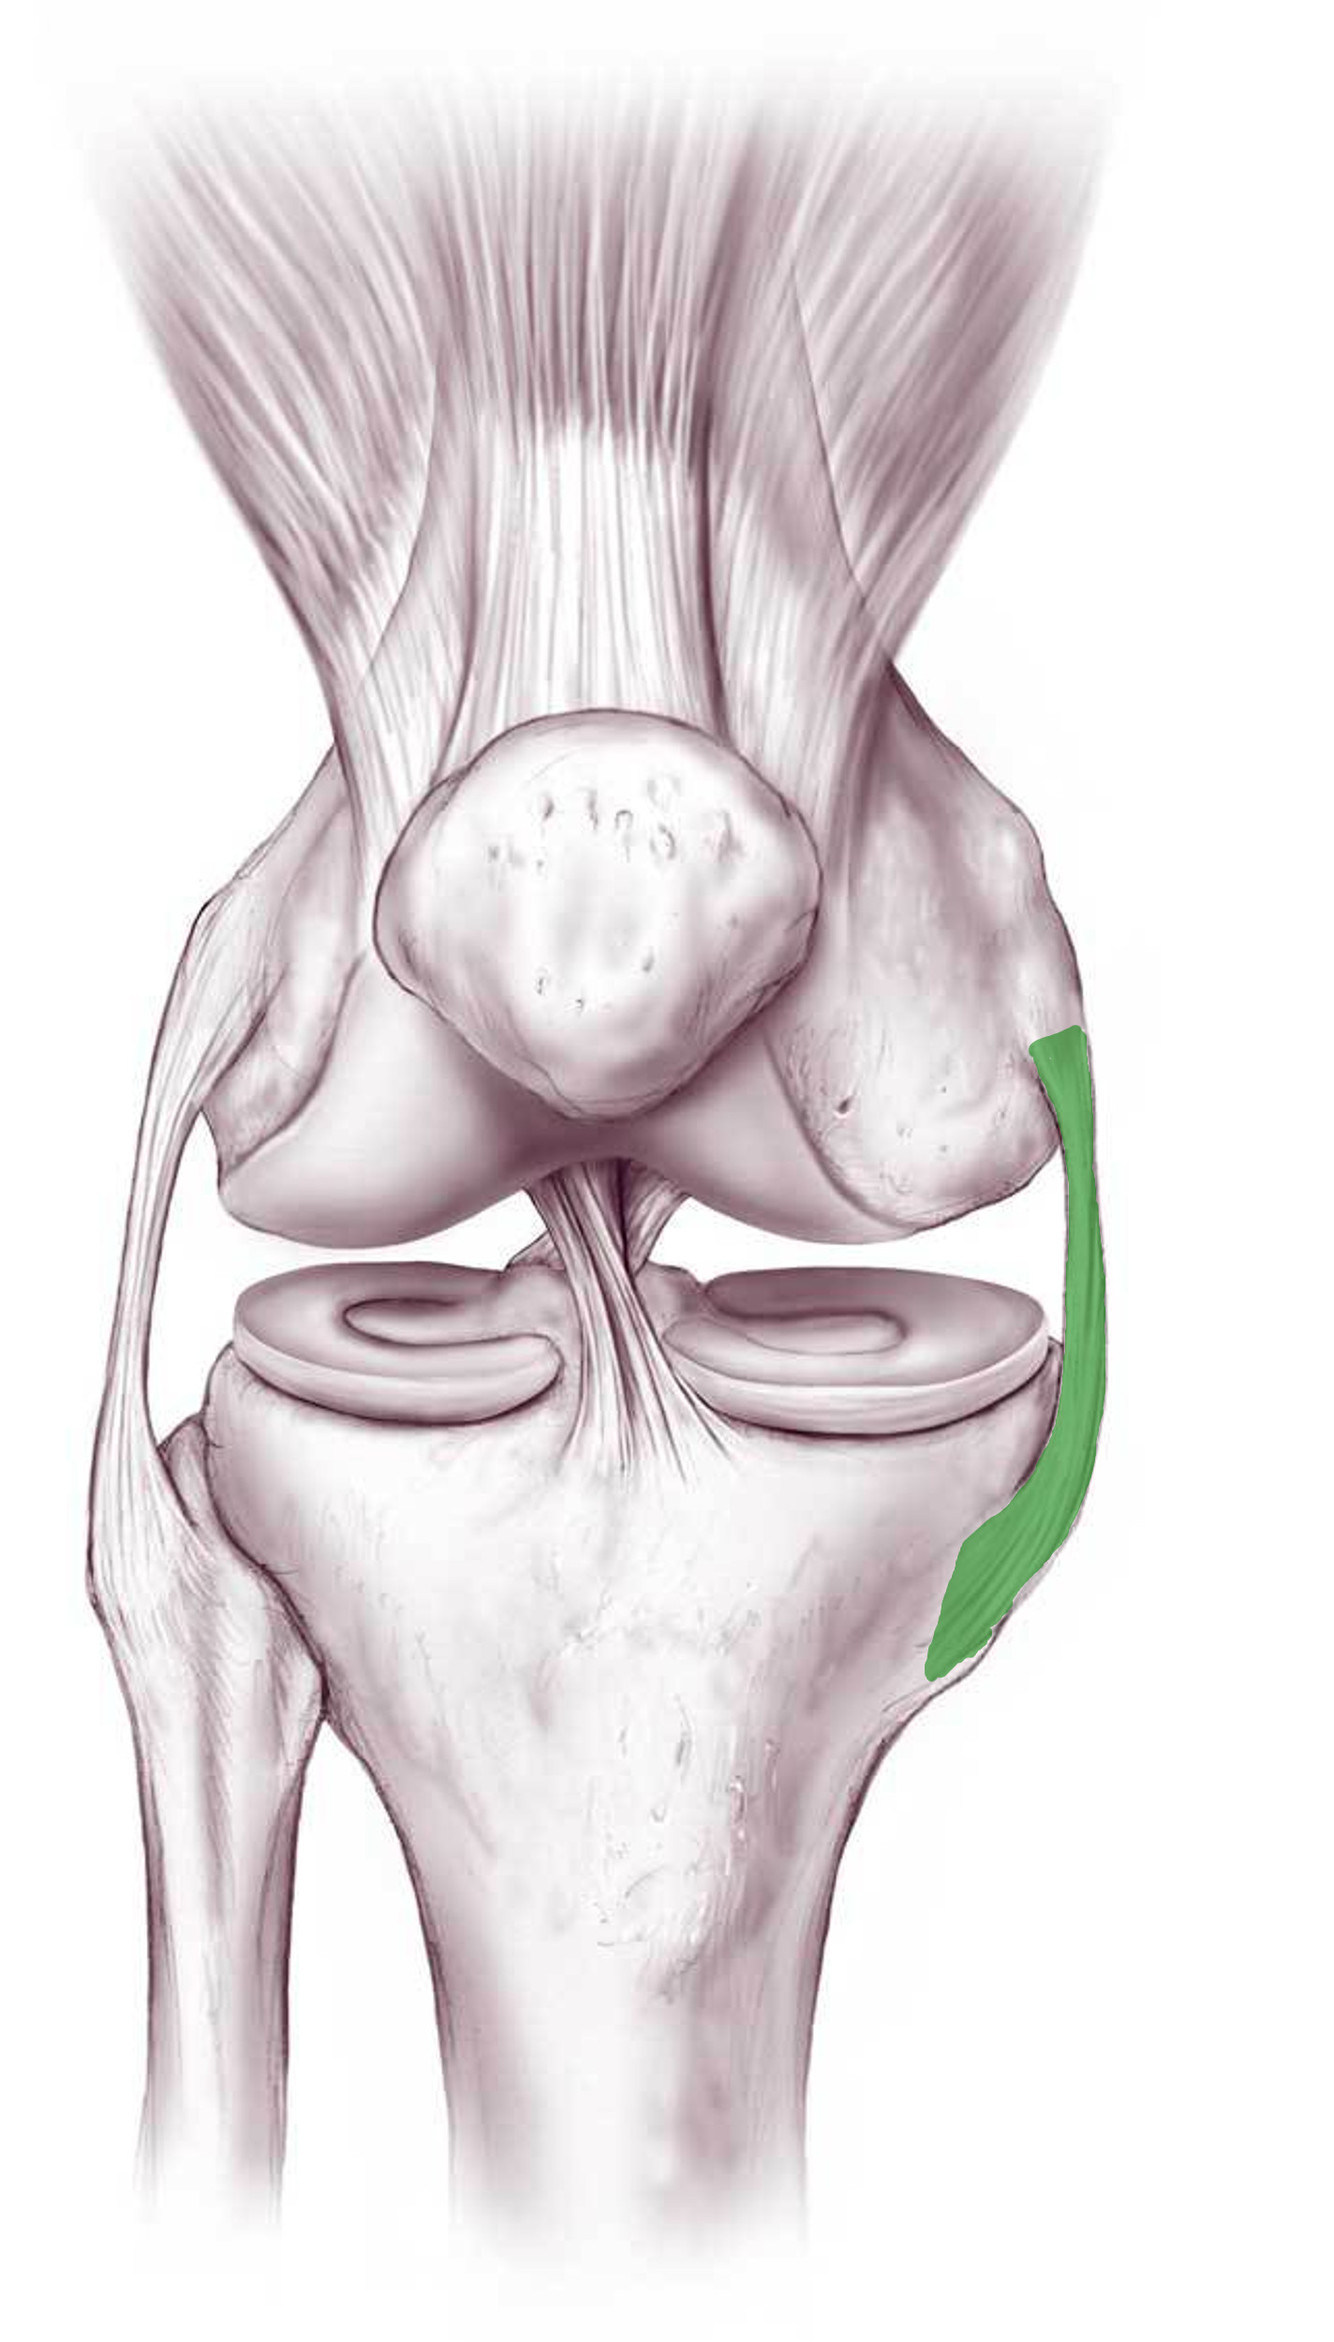

What is this structure?

Medial collateral ligament of the knee

Where does the medial collateral ligament extend to and from?

Medial epicondyle of femur

to medial condyle and upper part of medial surface of tibia